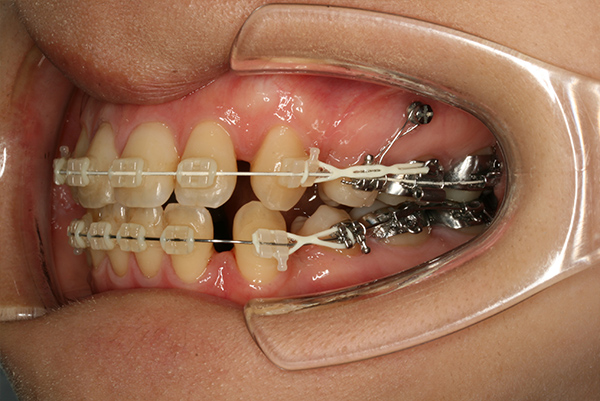

裁断済みとなっております。書き込み、マーカー等はございません。大きな目立った汚れはございません。- 著者: HYO-SANG PARK- 監修: 加藤直美- タイトル: アンカースクリューを用いた新しいMTM矯正- 内容: 補綴前矯正に関する技術と事例- 出版社: 永末書店ご覧いただきありがとうございます。月星歯科